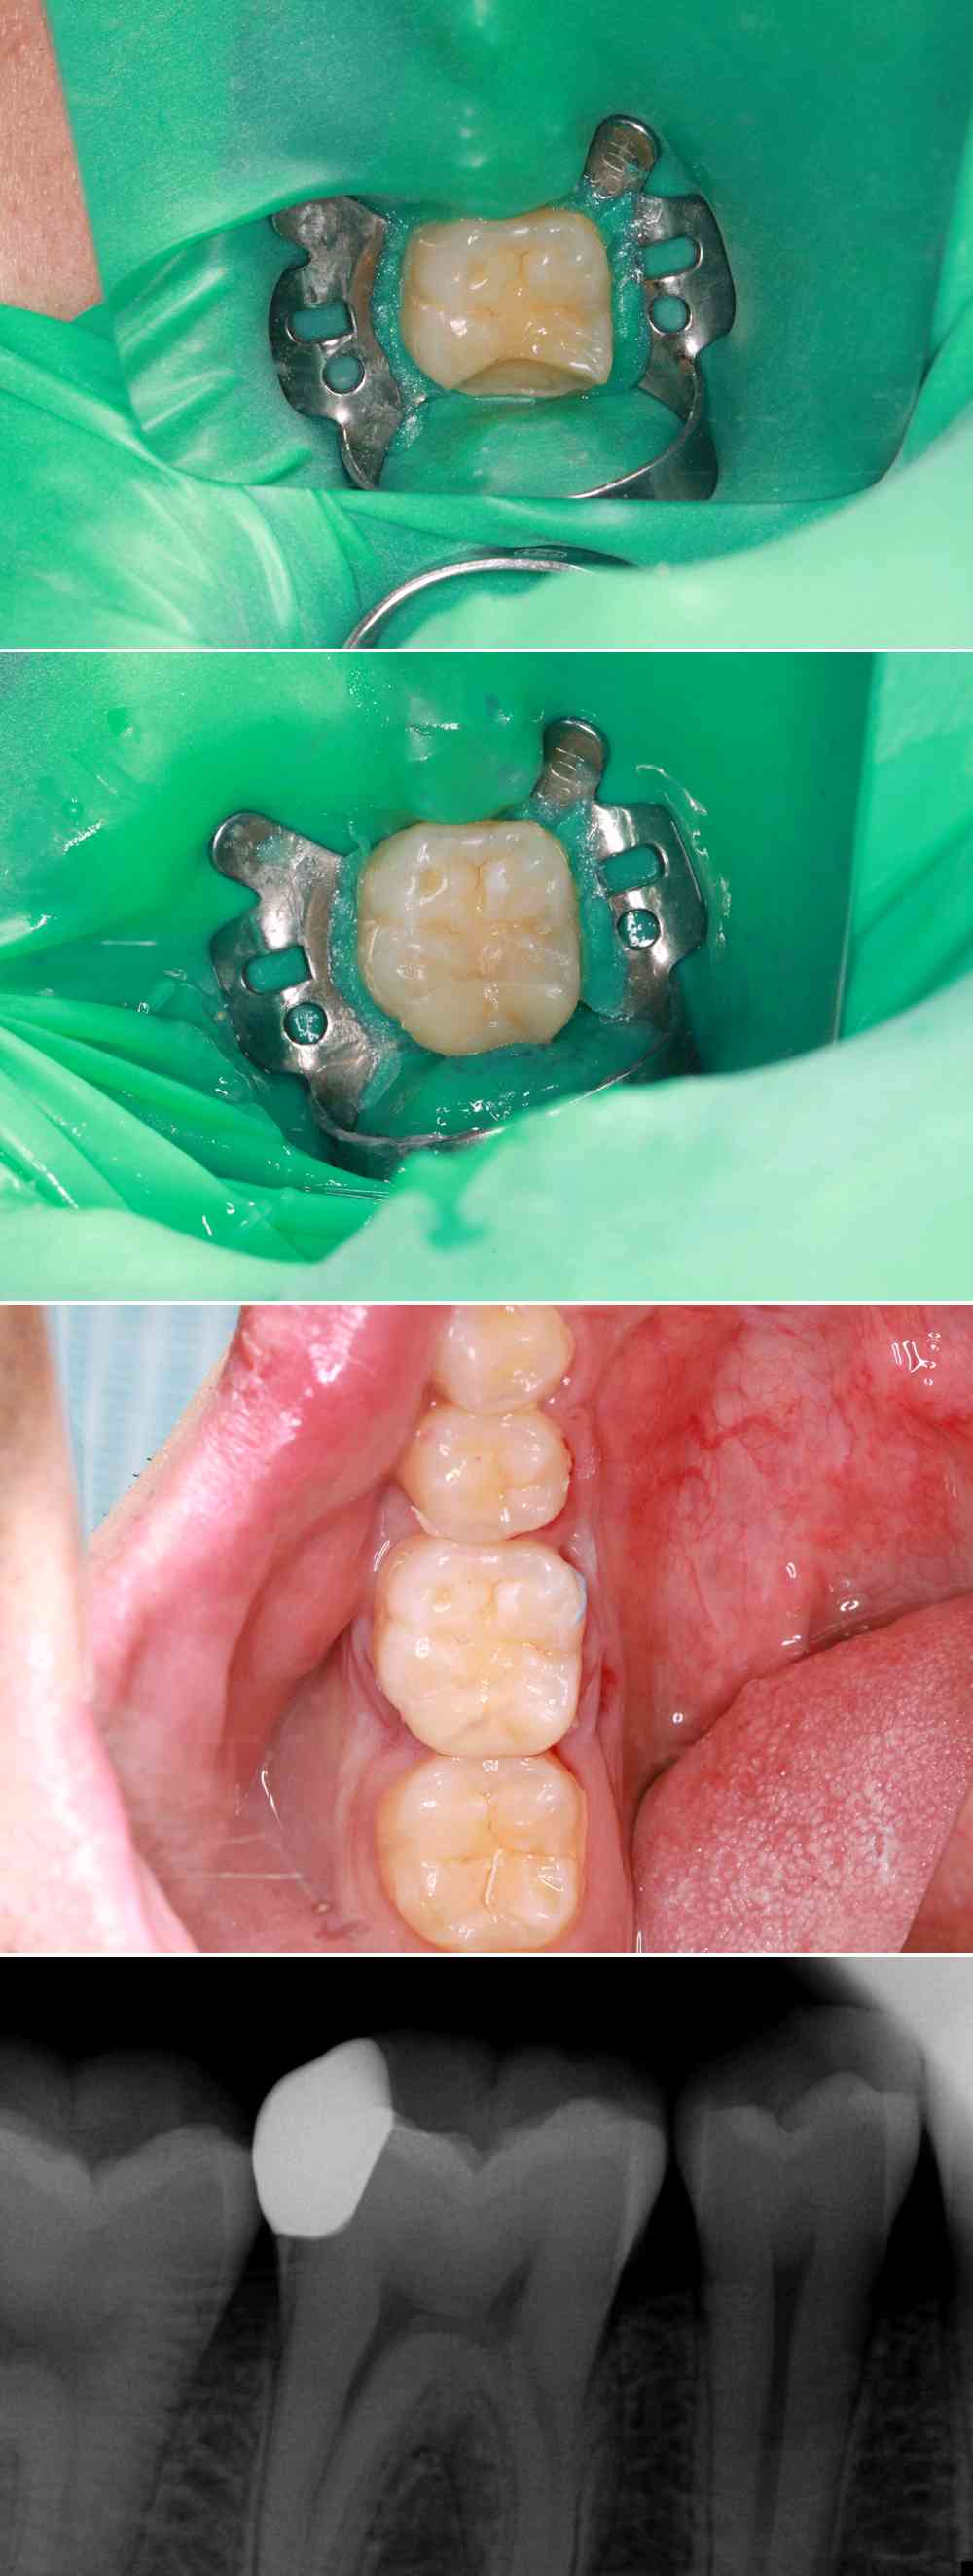

3、保护牙齿薄壁弱尖和隐裂,防止牙齿折裂和纵折。

4、邻面龋坏造成的缺损,能正确的恢复邻面接触点的部位,大小,松紧等。

(上图边缘恢复非常密合,触点非常好,不会引起食物嵌塞,酸痛。)

5、瓷嵌体具有更好的美学功能。

(上图牙预备量非常少,拼接修复和自己天然牙一样,无异物感美观)